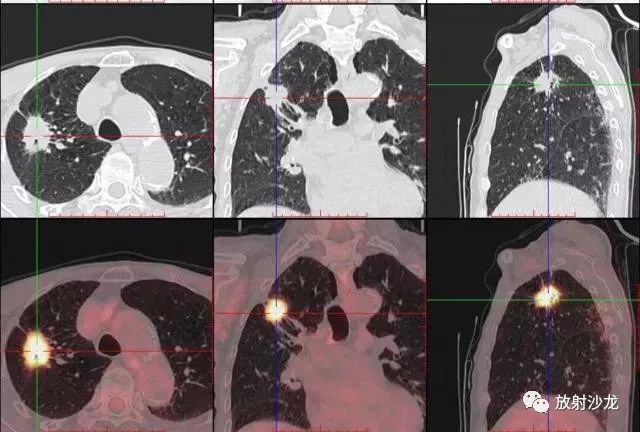

PET-CT是目前世界上最先進的核醫(yī)學分子影像設備,中文稱為正電子發(fā)射計算機斷層/X 線計算機體層成像。

PET-CT等于PET+CT,包含PET(功能分子影像)與CT(解剖影像)的最優(yōu)化組合;即同時具有PET和CT的功能,但它絕不是二者功能的簡單疊加,因為PET與CT優(yōu)勢互補,“1+1>2”。PET-CT除了具備PET和CT各自的功能外,其獨有的融合圖像,將PET圖像與CT圖像融合, 可以同時反映病灶的代謝,可以早期診斷疾病的同時,明顯提高診斷的準確性。

18F-FDG(氟脫氧葡萄糖)是葡萄糖的類似物,是臨床最常用的顯像劑;18F-FDG能反映體內葡萄糖利用狀況。腫瘤細胞內可積聚大量18F-FDG,但是18F-FDG僅僅是葡萄糖類似物,腫瘤細胞攝取后不能進一步代謝,屬于“只進不拉”,能在腫瘤細胞內積聚,經(jīng)PET-CT顯像可顯示腫瘤的部位、形態(tài)、大小、數(shù)量及腫瘤內的放射性分布。同時腫瘤細胞的原發(fā)灶和轉移灶具有相似的代謝特性,一次注射18F-FDG就能方便地進行全身顯像,18F-FDG PET-CT全身顯像對于了解腫瘤的全身累及范圍具有獨特價值。